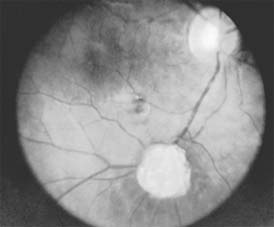

Retinoblastoma (Figure 10-32)

Figure 10-32

Figure 10-32: Retinoblastoma as viewed through the pupil.